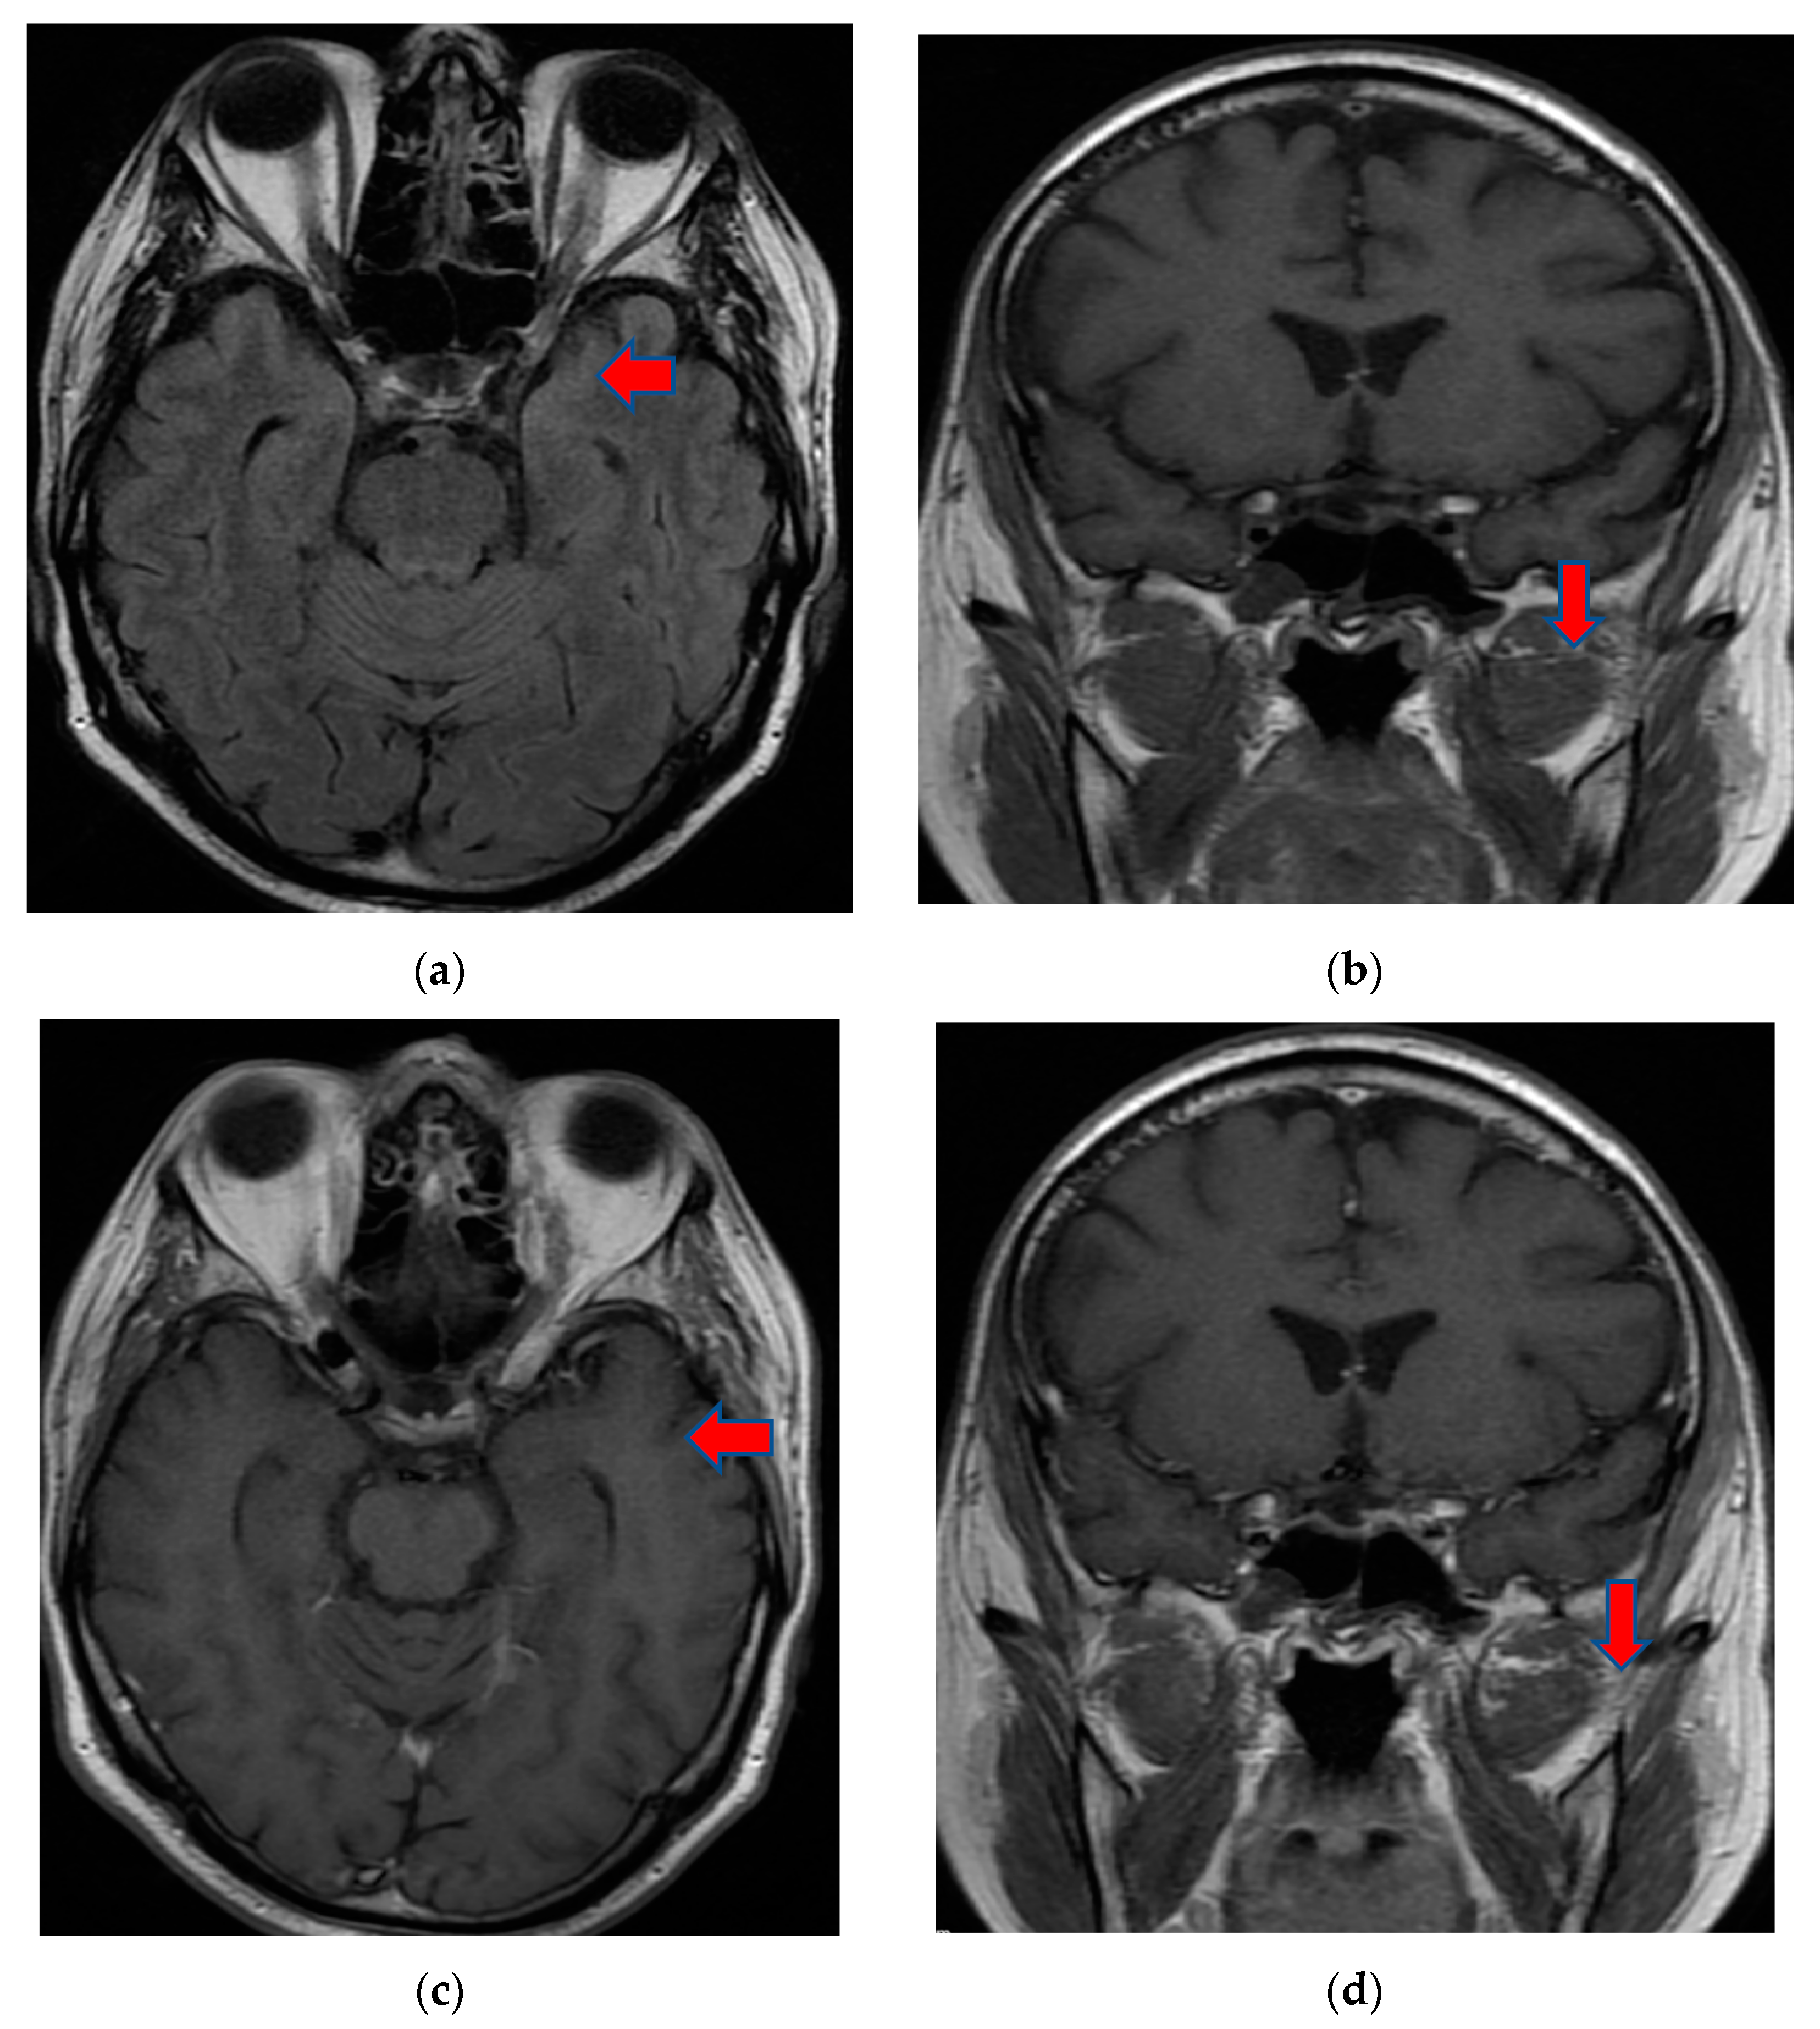

The patient continued to have worsening encephalopathy, and, after seven days, he presented with a depressed level of consciousness and extreme agitation. A repeat MRI brain scan with and without contrast showed extension of the lesion in the left fronto-parieto-temporal lobes with hypersignal aspects on the T2, Flair, and DWI images. Small hemorrhagic lesions were also shown in the left temporal lobe (hyperintense on T2 images) and in the posterior limb of the internal capsule. A hyperdense aspect capturing the contrast of the left middle cerebral artery wall was highlighted. The appearance was suggestive of the infectious/autoimmune vasculitis. The fronto-parieto-temporal meninges showed contrast capture on the Flair images (Figure 3).

Figure 3.

MRI T2 axial Flair (a) and axial DWI (b) images demonstrated extension of the lesion in the fronto-parieto-temporal left lobes. Coronal T1 FSE (c) and axial T1 FSE (d) with contrast showing a hyperdense aspect of the left middle cerebral artery wall, suggestive of infectious/autoimmune vasculitis.